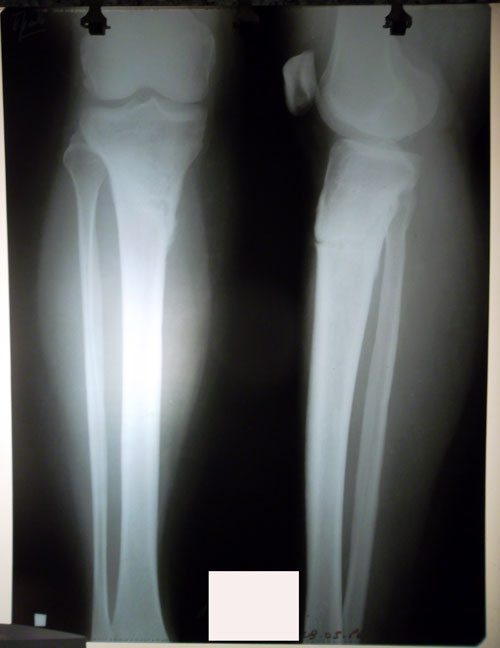

Рентген контроль в 1,5 месяца после снятия аппаратов.

сращение отличное, разрешены постепенно возрастающие нагрузки и каблуки.